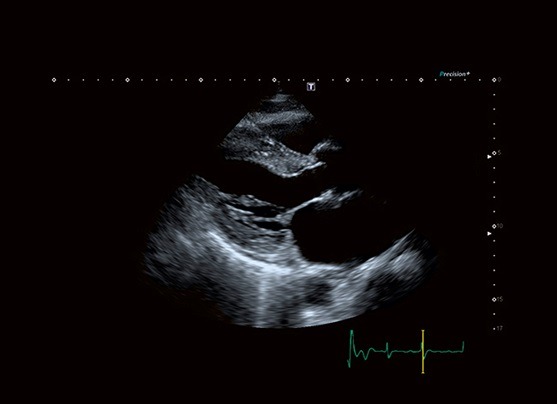

Tissue Enhancement تصاویری با یکنواختی و وضوح حیرت انگیز و نمایش بهبود یافته ای از مرزهای قلبی، بالاخص برای بیماران با شرایط سخت، ارائه می‌دهد.